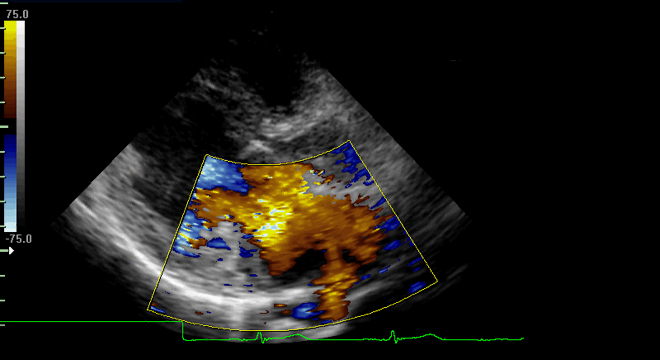

Herzmuskelentzündung: Echokardiographie (Herz-Ultraschall)

• Echokardiographie (Herzultraschall-Untersuchung)